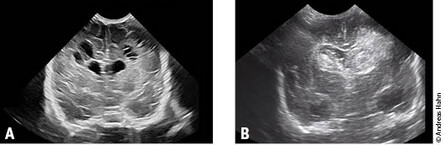

Unter einer infantilen Zerebralparese (ICP) versteht man eine Bewegungsstörung, häufig in Form einer Spastik, die entweder intrauterin oder kurz nach Geburt eingetreten ist, die nicht progredient ist, und häufig mit anderen Komorbiditäten, z. B. Intelligenzminderung oder Epilepsie, assoziiert ist. Während die ICP früher meist auf einen Sauerstoffmangel bei Geburt zurückzuführen war, dominieren heutzutage Komplikationen bei Frühgeburtlichkeit wie Hirnblutung oder periventrikuläre Leukomalazie (Abb. 2 A + B).

Abb.2 A + B: Schädelsonographisch ausgeprägte bilaterale periventrikuläre polyzystische Veränderungen im Rahmen einer Leukomalazie bei einem Frühgeborenen der 24. Schwangerschaftswoche (A). Bilaterale, linksbetonte Hirnblutung bei einem Frühgeborenen der 26. Schwangerschaftswoche (B).